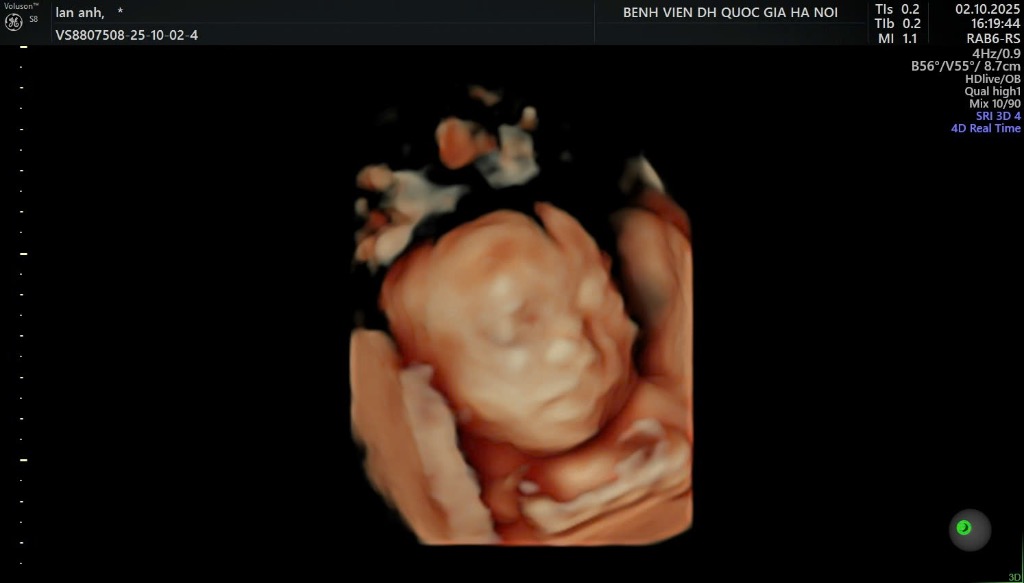

Đào Thị Nhung